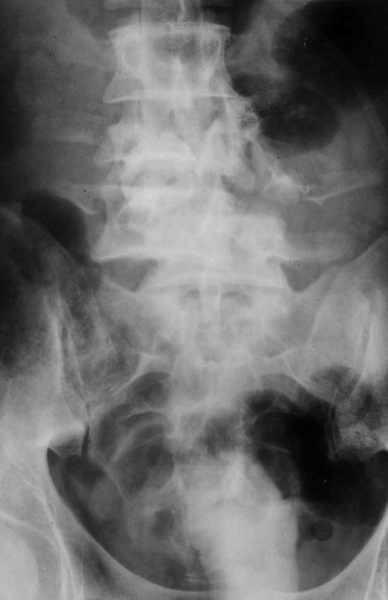

Высылаю рентгенограммы. Спасибо за рекомендации. Наша тактика согласуется с вашими рекомендациями за исключением транспедикулярной фиксации - у данного пациента на наш взгляд предпочтительнее наружная транспедикулярная фиксация (Курганский аппарат). Погружная конструкция предпологает одномоментную репозицию до выполнения забрюшинного доступа и ревизии переломов что теоретически может привести к повреждению дурального мешка и корешков. АВФ позволит восстановить ось позвоночника и смещение по длине непосредственно под контролем глаза на этапе внебрюшинного доступа. Сколько сегментов замыкать? Я думаю может потребоваться замкнуть и сегмент L2-L3. Предполагается использовать тело L4 для костной пластики таким образом, чтобы ширина спиномозгового канала на уровне оперированных сегментов была увеличена. Фиксация тел позвонков вентральной пластиной.

Если в вышей практике встечались подобные случаи прошу подробнее их описать.